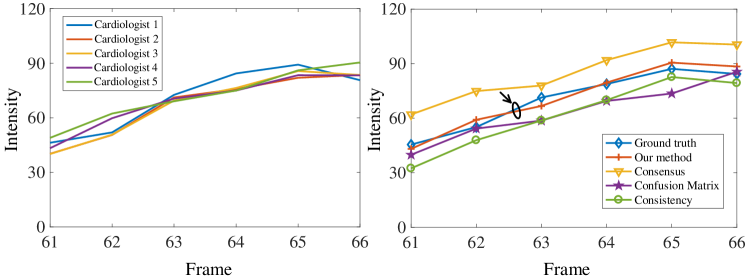

Evaluation using frame-intensity curve: In order to show that the proposed extended Dice and loss function are indeed superior from the clinical application perspective, we also use the frame-intensity curve of segmented myocardium, which is commonly used in myocardial perfusion analysis [10, 5], to evaluate the segmentation performance. Frame-intensity curve, also known as the time-intensity curve, can be used to reflect the relative microvascular blood volume after microbubbles infusion, thus help estimate myocardial ischemia. Fig. 3 shows the frame-intensity curves of six frames of a subject (Frame 61-66) using the annotations from each of the five cardiologists (left), and from the top four methods in Table 3, namely our method, Consensus, Confusion Matrix and Consistency (right). U-Net is used as the segmentation framework. Although the annotations from the five cardiologists are very different as shown in Table 1, from the left figure we can see that the resulting frame-intensity curve from each of them are very similar to each other. Based on this observation, we obtain a ground truth frame-intensity curve through averaging. It can be seen in the right figure that among all the four methods compared, the curve generated by our method is the closest to the ground truth curve. This convincingly shows that our method can better help myocardial perfusion analysis.